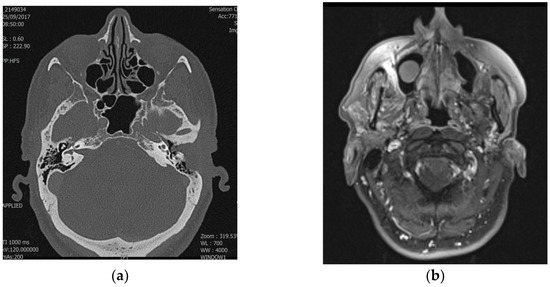

Decoding Temporal Bone Carcinoma: The Role of CT and MRI in Precision Staging

Primary squamous cell carcinoma (SCC) of the temporal bone is an extremely rare malignancy, comprising only 0.2% of head and neck cancers. There is currently no universally accepted staging system for these tumors. This study evaluates the utility of the Pittsburgh staging system [...] Read more.

Primary squamous cell carcinoma (SCC) of the temporal bone is an extremely rare malignancy, comprising only 0.2% of head and neck cancers. There is currently no universally accepted staging system for these tumors. This study evaluates the utility of the Pittsburgh staging system for temporal bone SCC, examines prognostic factors, and reports clinical outcomes. A retrospective review was conducted on a small cohort of 15 patients diagnosed with temporal bone SCC between 2020 and 2023. Imaging included high-resolution CT and MRI (T1W, T2W, and DWI). Staging accuracy was assessed, and Cohen’s Kappa coefficient was used to compare radiological and pathological staging. Results showed a 73% accuracy in preoperative radiological staging, with higher agreement for T3/T4 tumors (86%) compared to T1/T2 (63%). MRI provided additional information, revealing dural enhancement in two patients and parotid involvement in one. Survival analysis indicated 100% survival in T1/T2 patients, 25% in T3, and 0% in T4, supporting the prognostic value of the Pittsburgh system. While limited by the small sample size, the study confirms that the Pittsburgh staging system offers a reliable approach to stratifying patients with temporal bone SCC and underscores the importance of combined CT and MRI for accurate staging and treatment planning. Full article